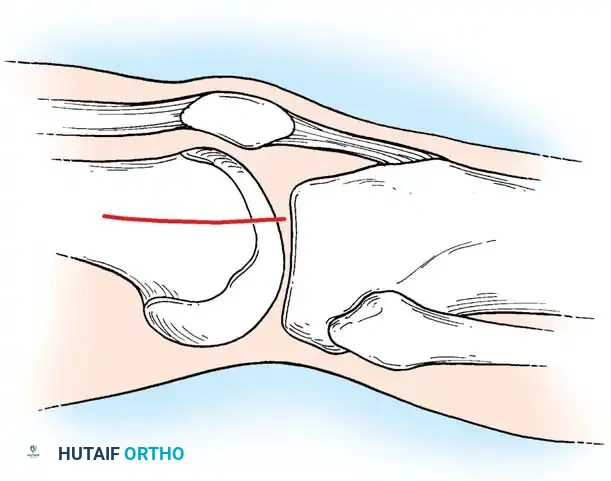

Rosenberg specifically identified that osteochondral fractures of the lateral femoral condyle are disproportionately common in adolescent boys. The primary biomechanical mechanism is often a transient lateral dislocation of the patella. As the patella relocates, it shears off a fragment of the lateral femoral condyle. Because these fragments possess a strong tendency to migrate and cause mechanical symptoms (locking, catching, and accelerated chondrolysis), surgical intervention is almost universally required.

The primary goal of surgery is the anatomical restoration of the articular surface to prevent early-onset osteoarthritis. If the fragment involves a weight-bearing surface and possesses sufficient attached subchondral bone to allow for osseous healing, internal fixation is strictly recommended.

Surgical Warning: If diagnosis and surgery are significantly delayed, the edges of the osteochondral fragment and the donor defect will become rounded, making exact anatomical reduction impossible. In such chronic cases, the fragment must be excised. The cancellous bed of origin should be meticulously smoothed, and any detached or frayed edges of adjacent articular cartilage must be excised sharply and vertically—never beveled or shaved down—to create stable, perpendicular cartilage walls.